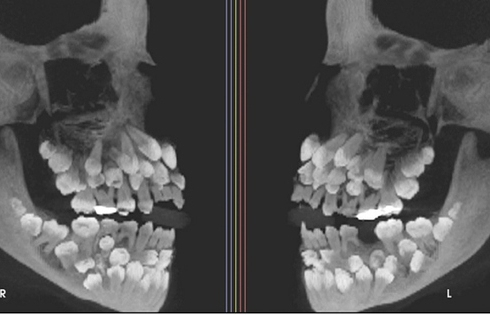

Đi nhổ răng sữa, bé gái khiến nha sĩ sốc nặng khi có 81 chiếc răng

Đi nhổ răng sữa, một bé gái 11 tuổi đã khiến nha sĩ sốc nặng khi phát hiện phim chụp X-quang cho thấy cô bé có 81 chiếc răng trong miệng.